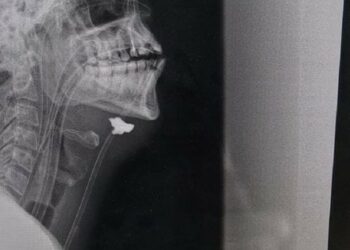

Lvovští lékaři v jedné z frontových nemocnic zachránili život třicetiletému kapitánovi, který byl na frontě vážně zraněn. Úlomek projektilu zasáhl ...